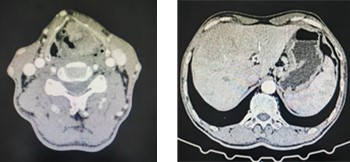

按照肿瘤全身性疾病诊疗原则,放疗一科为其完善胸腹部CT评估,结果提示“胃壁增厚伴多发胃周淋巴结转移”。这一发现引起了副主任医师王晓东的高度警觉。凭借三十余年临床经验,他敏锐判断这可能并非单一喉癌转移,而是极为罕见的“双原发恶性肿瘤”。经胃镜活检证实,第二原发灶——“胃腺癌”得以明确诊断。至此,患者最终确诊为喉鳞癌伴颈部淋巴结转移、胃腺癌伴胃周淋巴结转移。

左图为喉部肿瘤,右图为胃壁增厚并胃周淋巴结增大